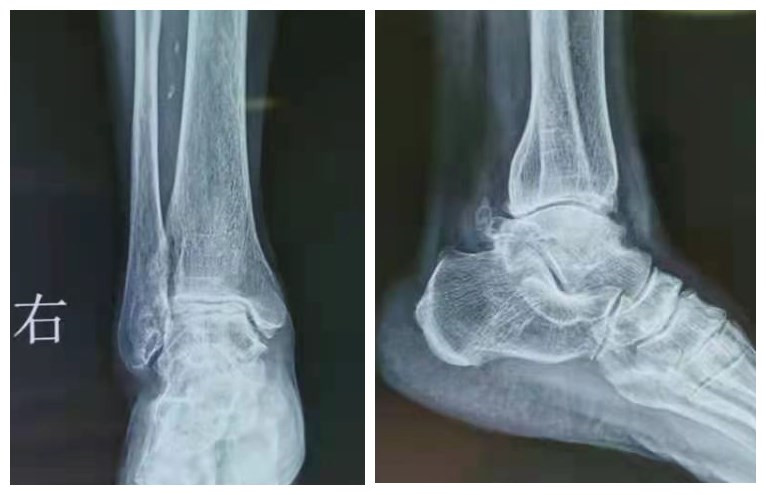

患者术前右踝X线片

踝关节置换术后X线片